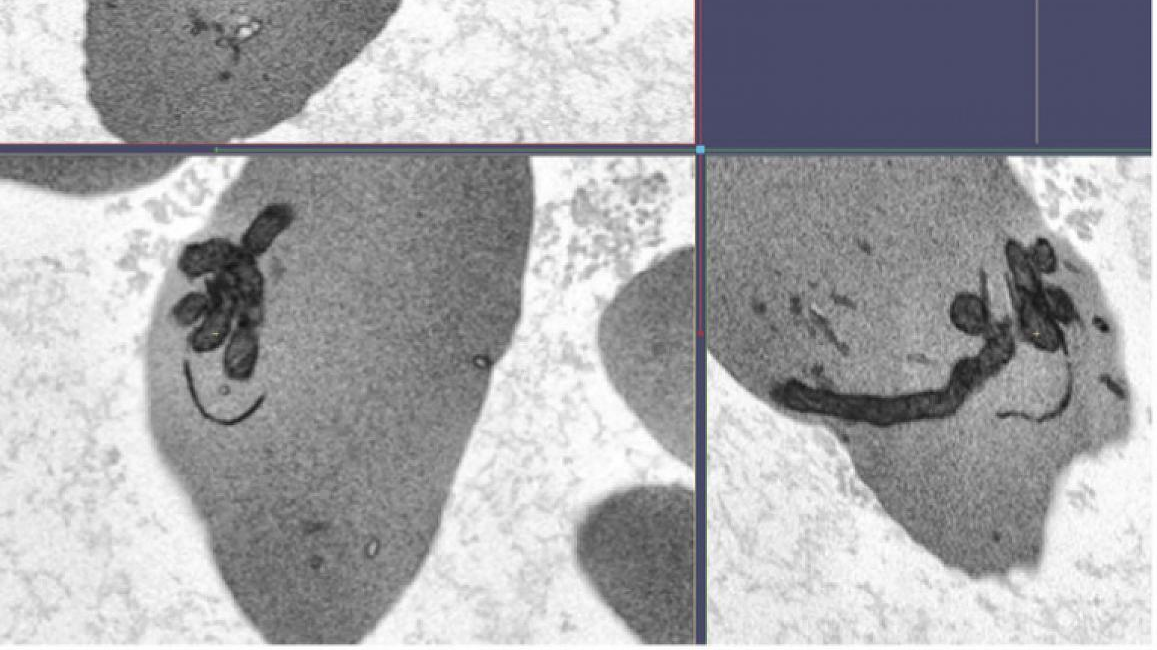

Normally a red blood cell gets rid of its mitochondria when it matures, because the energy from mitochondria is not needed to carry out the red blood cell’s function of delivering oxygen throughout the body. However, Thein and her team showed that red blood cells from people with sickle cell anemia - the most common and often most severe type of sickle cell disease - abnormally retain the mitochondria, which can lead to a buildup of highly reactive chemical molecules that stresses the cells.

This condition, researchers found, allows damaged mitochondrial DNA to enter circulation with too few of the small molecules, called methyl groups, that typically attach to the DNA to help the cells function. This abnormal amount of molecules on the mitochondrial DNA, in turn, stimulates inflammation, a hallmark of sickle cell disease.